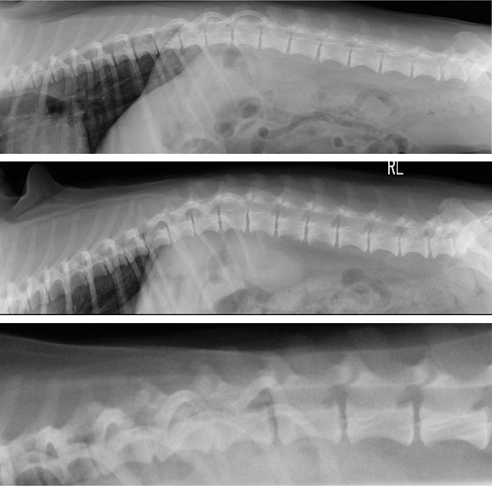

【画像診断】~ダックスフンド、雄10歳、グレート3の椎間板ヘルニア~

▲ダックスフンド、病変部は胸椎T13-腰椎L1の単純X線検査像の側面像